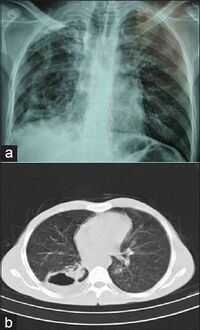

a,b)Mycobacterium branderi- chest radiograph, chest computed tomography

The first strains of M. branderi were isolated from samples obtained from nine patients, some of whom had cavitary mycobacteriosis of the lungs that was resistant to available drugs. In most cases, repeat samples obtained from each patient were positive for acid-fast bacilli as determined by microscopy, and the only cultivable species was M. branderi. M. branderi has to be considered a potential human pathogen.